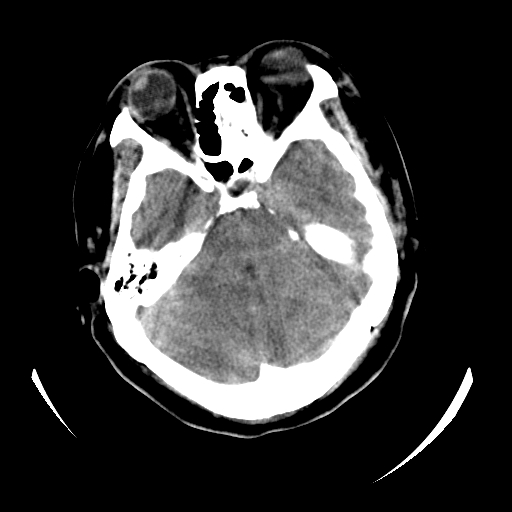

女,53岁,发现昏迷1天,血压不高,有精神病史。临床诊断:脑梗死?

ct诊断:1、双侧基底节区对称性脑梗塞。

2、双侧额叶、枕叶广泛密度减低,考虑缺血梗塞可能性大。

3、脑池小,脑沟浅,提示颅内高压。

测左枕叶白质ct值 约22hu 。请各位老师给出恬当诊断。

征象:病变呈对称性分布于双侧大脑半球,累及范围广泛,白质较灰质密度减低更为明显;脑沟变浅,脑池变窄;